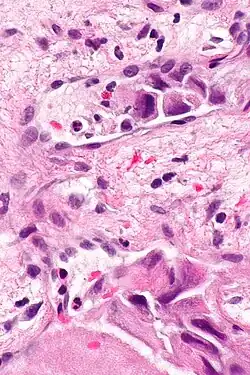

Lymphovascular invasion

Lymphovascular invasion (LVI or lymphovascular space invasion) is the invasion of a cancer to the blood vessels and/or lymphatics.

Pathology

Lymphovascular invasion, especially in carcinomas, usually precedes spread to the lymph nodes that drain the tissue in which the tumour arose. Conversely, cancers with lymph node spread (known as a lymph node metastases), usually have lymphovascular invasion. Lymph node metastases usually precede secondary tumours, i.e. distant metastases.